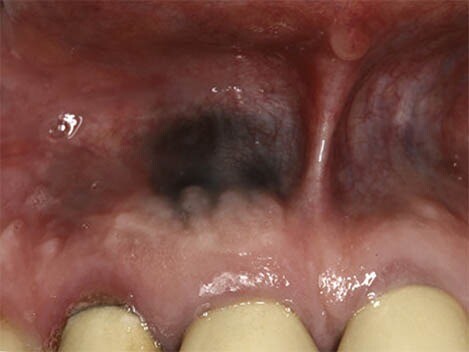

What Causes a Black Spot on Your Gums?

First, we recommend taking a moment to breathe and relax. According to the Oral Cancer Foundation, dark spots rarely indicate a serious condition like cancer and are usually benign. Spots in the mouth are often not fully black but may appear that way as they can be hard to see. We’re here to help walk you through the causes of dark spots in your mouth and what they mean.

Oral conditions like dark spots on your gums have various causes and can be challenging to diagnose. These spots can either be harmless or the result of an underlying disease, so it's essential to speak to your doctor if you believe you have any symptoms.

Internal pigments that cause skin colour changes can also modify your gums' colour to black, grey, blue, or brown. Blood vessels can even dysfunction or rupture, leading to discolouration.

According to a research article published in the Journal of Indian Academy of Oral Medicine and Radiology, haemangiomas are most common soft tissue benign tumours, composed of blood vessels, and occur in the head and neck region (60%) and less commonly in the oral cavity; oral cavity if affected involves gingiva followed by the lips, tongue and palate.

Oral Cancer

In rare cases, benign lesions that don't require treatment may transform into oral malignant melanoma, a type of oral cancer. A doctor will look at a range of factors to see if the lesion qualifies as melanoma. According to a research article published in the Journal of Indian Academy of Oral Medicine and Radiology, melanoma constitutes only 3–5% of all cutaneous malignancies, and oral melanoma is an aggressive neoplasm which accounts for less than 0.5%.